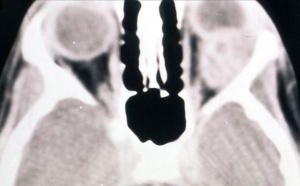

Patients generally present with proptosis (80-100%), globe displacement (80%), blepharoptosis (30-50%), conjunctival and eyelid swelling (60%), palpable mass (25%), ptosis (25%) and pain (10%) (Shields). Typically, orbital rhabdomyosarcomas present with rapidly developing unilateral exophthalmos over the course of weeks, however some cases may have a slower onset, with chronic eyelid and conjunctival edema being present before proptosis and globe displacement. Two thirds are superior or superonasal (Fig. 2), causing downward and outward displacement of the globe. Roughly ten percent arise from the paranasal sinuses (Fig. 3), nasal cavity, pterygopalatine fossa, and parapharyngeal space and secondarily invade the orbit, thus presenting with features of sinusitis, nasal obstruction, or epistaxis. Pain and decreased vision are minimal and are symptoms of more advanced disease. Epiphora is uncommon although nasolacrimal duct obstruction has been rarely reported.

Imaging

On CT scan (Fig. 3 & 4), the tumors appear as homogenous, well-circumscribed, round to ovoid masses, which are isodense to muscle. They are usually within the orbital soft tissues and do not appear to arise from the extraocular muscles. Earlier tumors do not invade bone, however larger tumors are less well defined and may erode bone and extend into the nasopharynx or sinuses. Areas of focal hemorrhage or necrosis may appear heterogeneous on CT scan. Rhabdomyosarcomas demonstrate moderate to marked contrast enhancement.